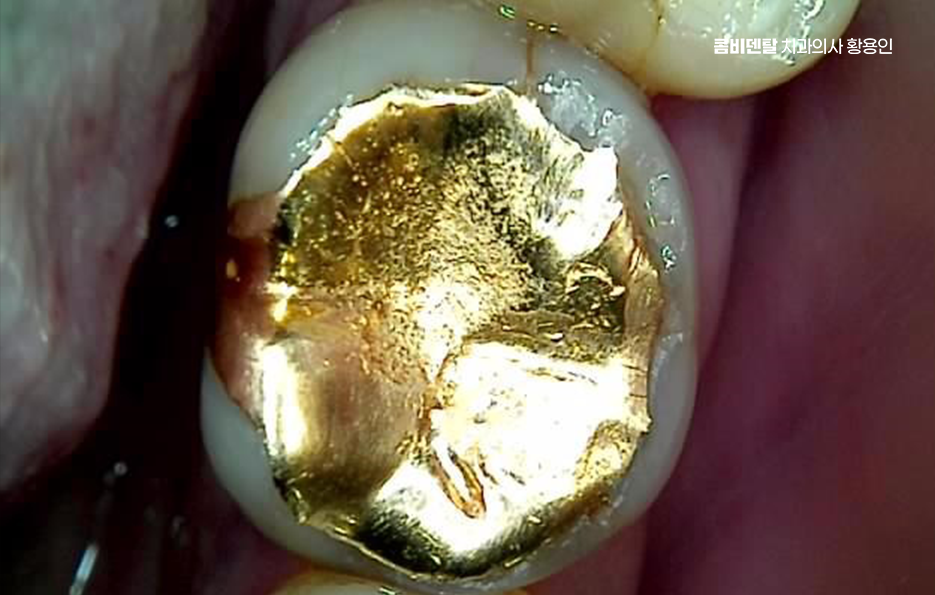

인레이 치료는 충치가 어느 정도 깊이 진행됐을 때 치아 형태를 유지하면서 기능을 회복하는 데 좋은 선택으로서 레진보다 강도는 높고, 크라운보다는 치아 삭제량이 적어서 중간 단계 치료로 자주 사용되는 방식이기도 한데 인레이 치료가 한 번 끝났다고 해서 그 치아가 완벽하게 안전해진 건 아니며 관리가 잘 안 되거나, 본인에게 맞지 않는 사용 습관이 반복되면 인레이를 했던 치아가 다시 충치가 생기거나, 보철물 혹은 주변 치아가 깨지면서 결국 신경치료까지 가는 경우도 있었어요

두 번째로는 보철물 자체가 파절되는 케이스로 인레이는 치아 만큼이나 강하지만 부서지지 않는 건 아닌데 특히 딱딱한 음식이나 얼음, 오징어 같은 질긴 걸 자주 씹는 습관이 있는 경우, 반복적인 교합 압력 때문에 인레이가 금이 가거나 쪼개지는 일이 생길 수 있으며 이때 보철물이 살짝 금 간 정도면 다시 본을 떠서 인레이를 교체하면 되는데 문제는 인레이가 파절되면서 그 안에 있는 치아 조직까지 손상시키는 경우로 치아는 한 번 금이 가기 시작하면 내부까지 확산되기 쉬워서, 그 틈을 따라 세균이 침입하고 결국 치수염, 즉 신경에 염증이 생기게 되는 거예요.

인레이 치료 후 신경치료 필요한 상황으로 진행됐다면, 보존할 수 있는 치아 구조가 얼마나 남아 있는지가 중요한데 신경치료 자체는 치아 내부를 소독하고, 염증 조직을 제거한 뒤, 충전하는 과정을 말하지만 신경치료를 하면 치아가 더 약해지고 부서지기 쉬워지기 때문에, 보통 그 위에 크라운을 씌워서 보호해줘야 하며 원래 인레이로 치료했던 치아가 결국 크라운 단계까지 가는 건데 이때 치아 삭제량도 많고 치료비도 올라가고, 원래 치아 구조는 더 많이 손상될 수 있었어요

그래서 보철 치료 후에는 치료가 끝났다고 끝이 아니고, 오히려 그때부터가 관리의 시작이라는 점을 기억해야 하며 꼭 지켜야 할 점은 치실 사용은 필수로 인레이와 같은 보철물은 사이드 접합부에 음식물이 끼기 쉬운데, 칫솔만으로는 제거가 안 되므로 하루에 한 번만이라도 치실을 쓰는 게 2차 충치 예방에 가장 효과적이며 딱딱한 음식 주의해야 하고 6개월~12개월에 한 번씩 정기검진 꼭 받는 것을 권장하는데 인레이 아래 충치나 균열은 본인이 느끼기 전까지는 모르기 때문에 조기 발견이 쉬운 방법이 바로 정기검진이라 할 수 있어요